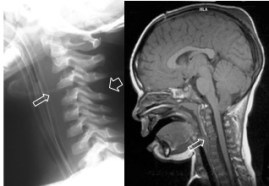

- le SCIWORA lié à la traction axiale sur la moelle, qui est moins compliante que le rachis